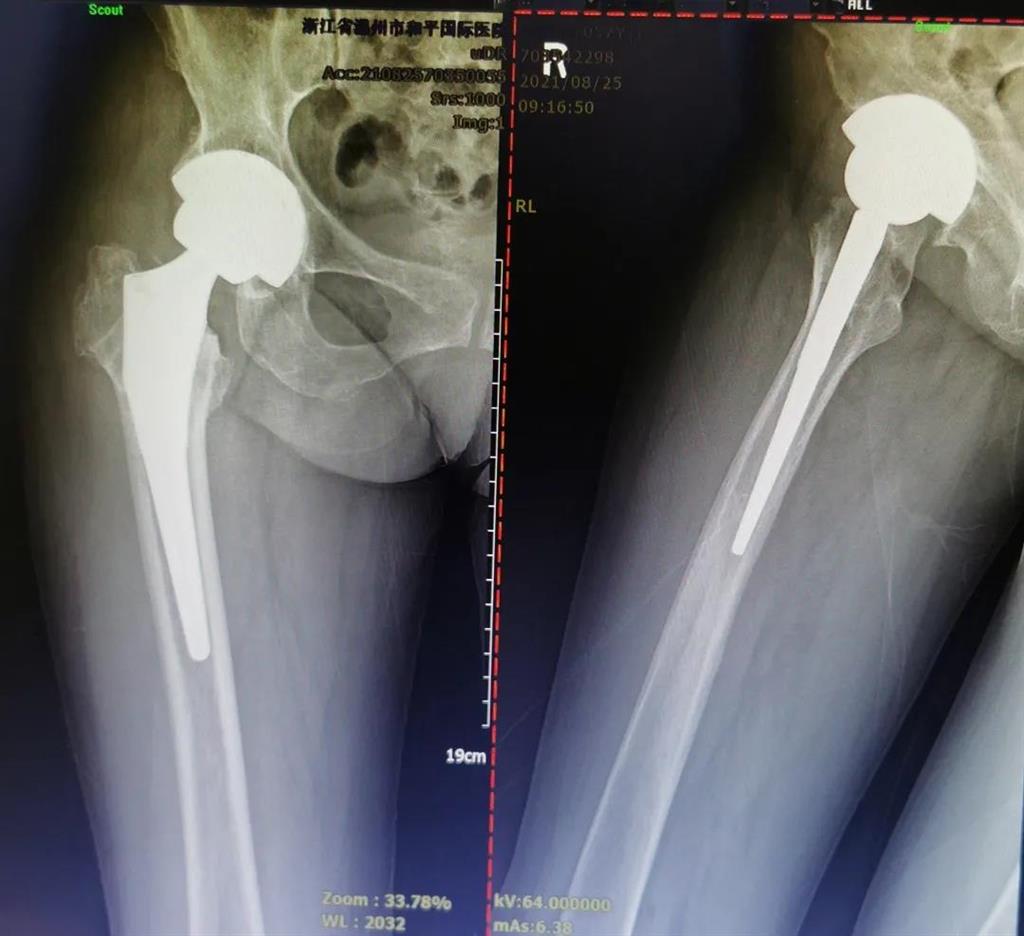

結(jié)合病癥表現(xiàn)及影像顯示,李女士被診斷為“右股骨頸骨折術(shù)后股骨頭壞死”,需要盡快做手術(shù)。

(△術(shù)前影像,右股骨頸骨折內(nèi)固定術(shù)后股骨頭壞死)